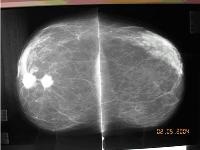

Dvě ložiska nádoru prsní žlázy